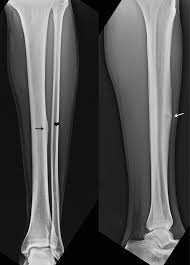

stress fracture

caused by overuse injury; tiny fracture lines

simple fracture

bone breaks but doesn't pierce the skin

spiral fracture

caused by twisting; break at an angle